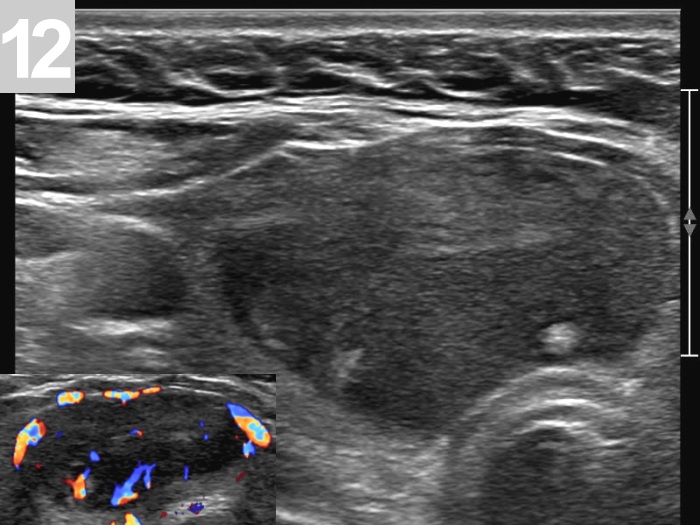

3 US of thyroid cancer

Pre- and postoperative ultrasound in thyroid cancers

Cases to be discussed on January 18, 2024